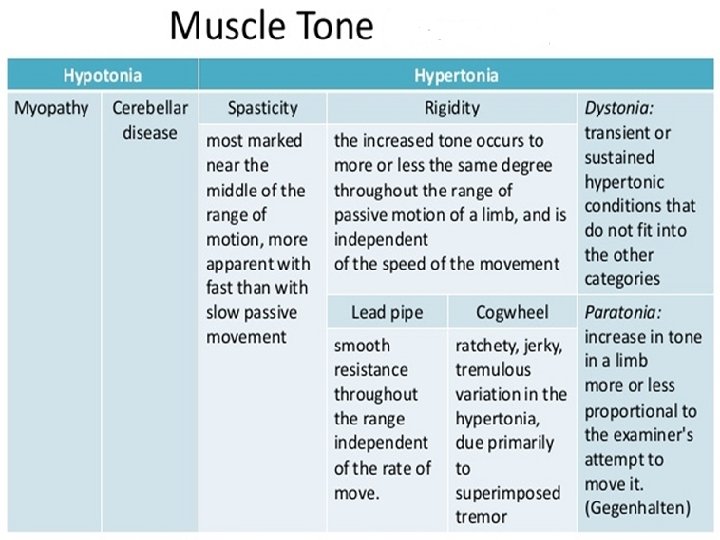

Changes In Tone And Tendon Reflexes Ø An acute lesion of one pyramidal tract (e. g. internal capsule stroke) causes initially FLACCID paralysis with loss of tendon reflexes. Ø Increase in tone follows, usually within several days due to loss of inhibitory effects of the corticospinal pathways and an increase in spinal reflex activity. Ø SPASTICITY is characterized by sudden changing resistance to passive movement – the clasp-knife effect. Ø Relevant TENDON REFLEXES become exaggerated; Ø CLONUS may emerge.

Extrapyramidal system The extrapyramidal system is a general term for BASAL GANGLIA motor systems, i. e. corpus striatum (caudate nucleus + globus pallidus + putamen), subthalamic nucleus, substantia nigra and parts of the thalamus. In basal ganglia/ extrapyramidal disorders, two features (either or both) become apparent, in limbs and axial muscles: Ø Reduction in speed (bradykinesia, meaning slow movement) or akinesia (no movement), with muscle rigidity Ø Involuntary movements (e. g. tremor, chorea, hemiballismus, athetosis, dystonia).